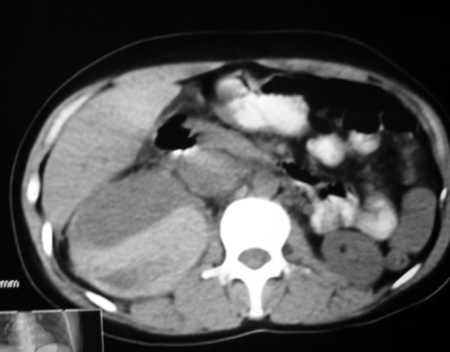

以下是引用bmw011在2009-4-23 13:28:00的发言:[br]考虑右肾包膜下血肿。

以下是引用卜一在2009-4-23 15:43:00的发言:[br]考虑右肾包膜下血肿,不排除占位病变伴出血可能,建议进一步检查。